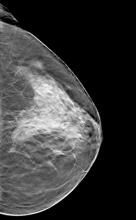

With ever-increasing concerns about radiation dose and the appropriate use of diagnostic imaging tests, doctors are continuously looking for ways to better image their patients. Advances in ultrasound are making the technology appear more attractive for certain clinical applications, from breast health to cardiology, thanks to their noninvasiveness, cost-effectiveness and lack of radiation. Some of the emerging innovations in ultrasound, such as real-time 3-D imaging and the development of wireless transducers, are set to keep the market going throughout 2013 and beyond.